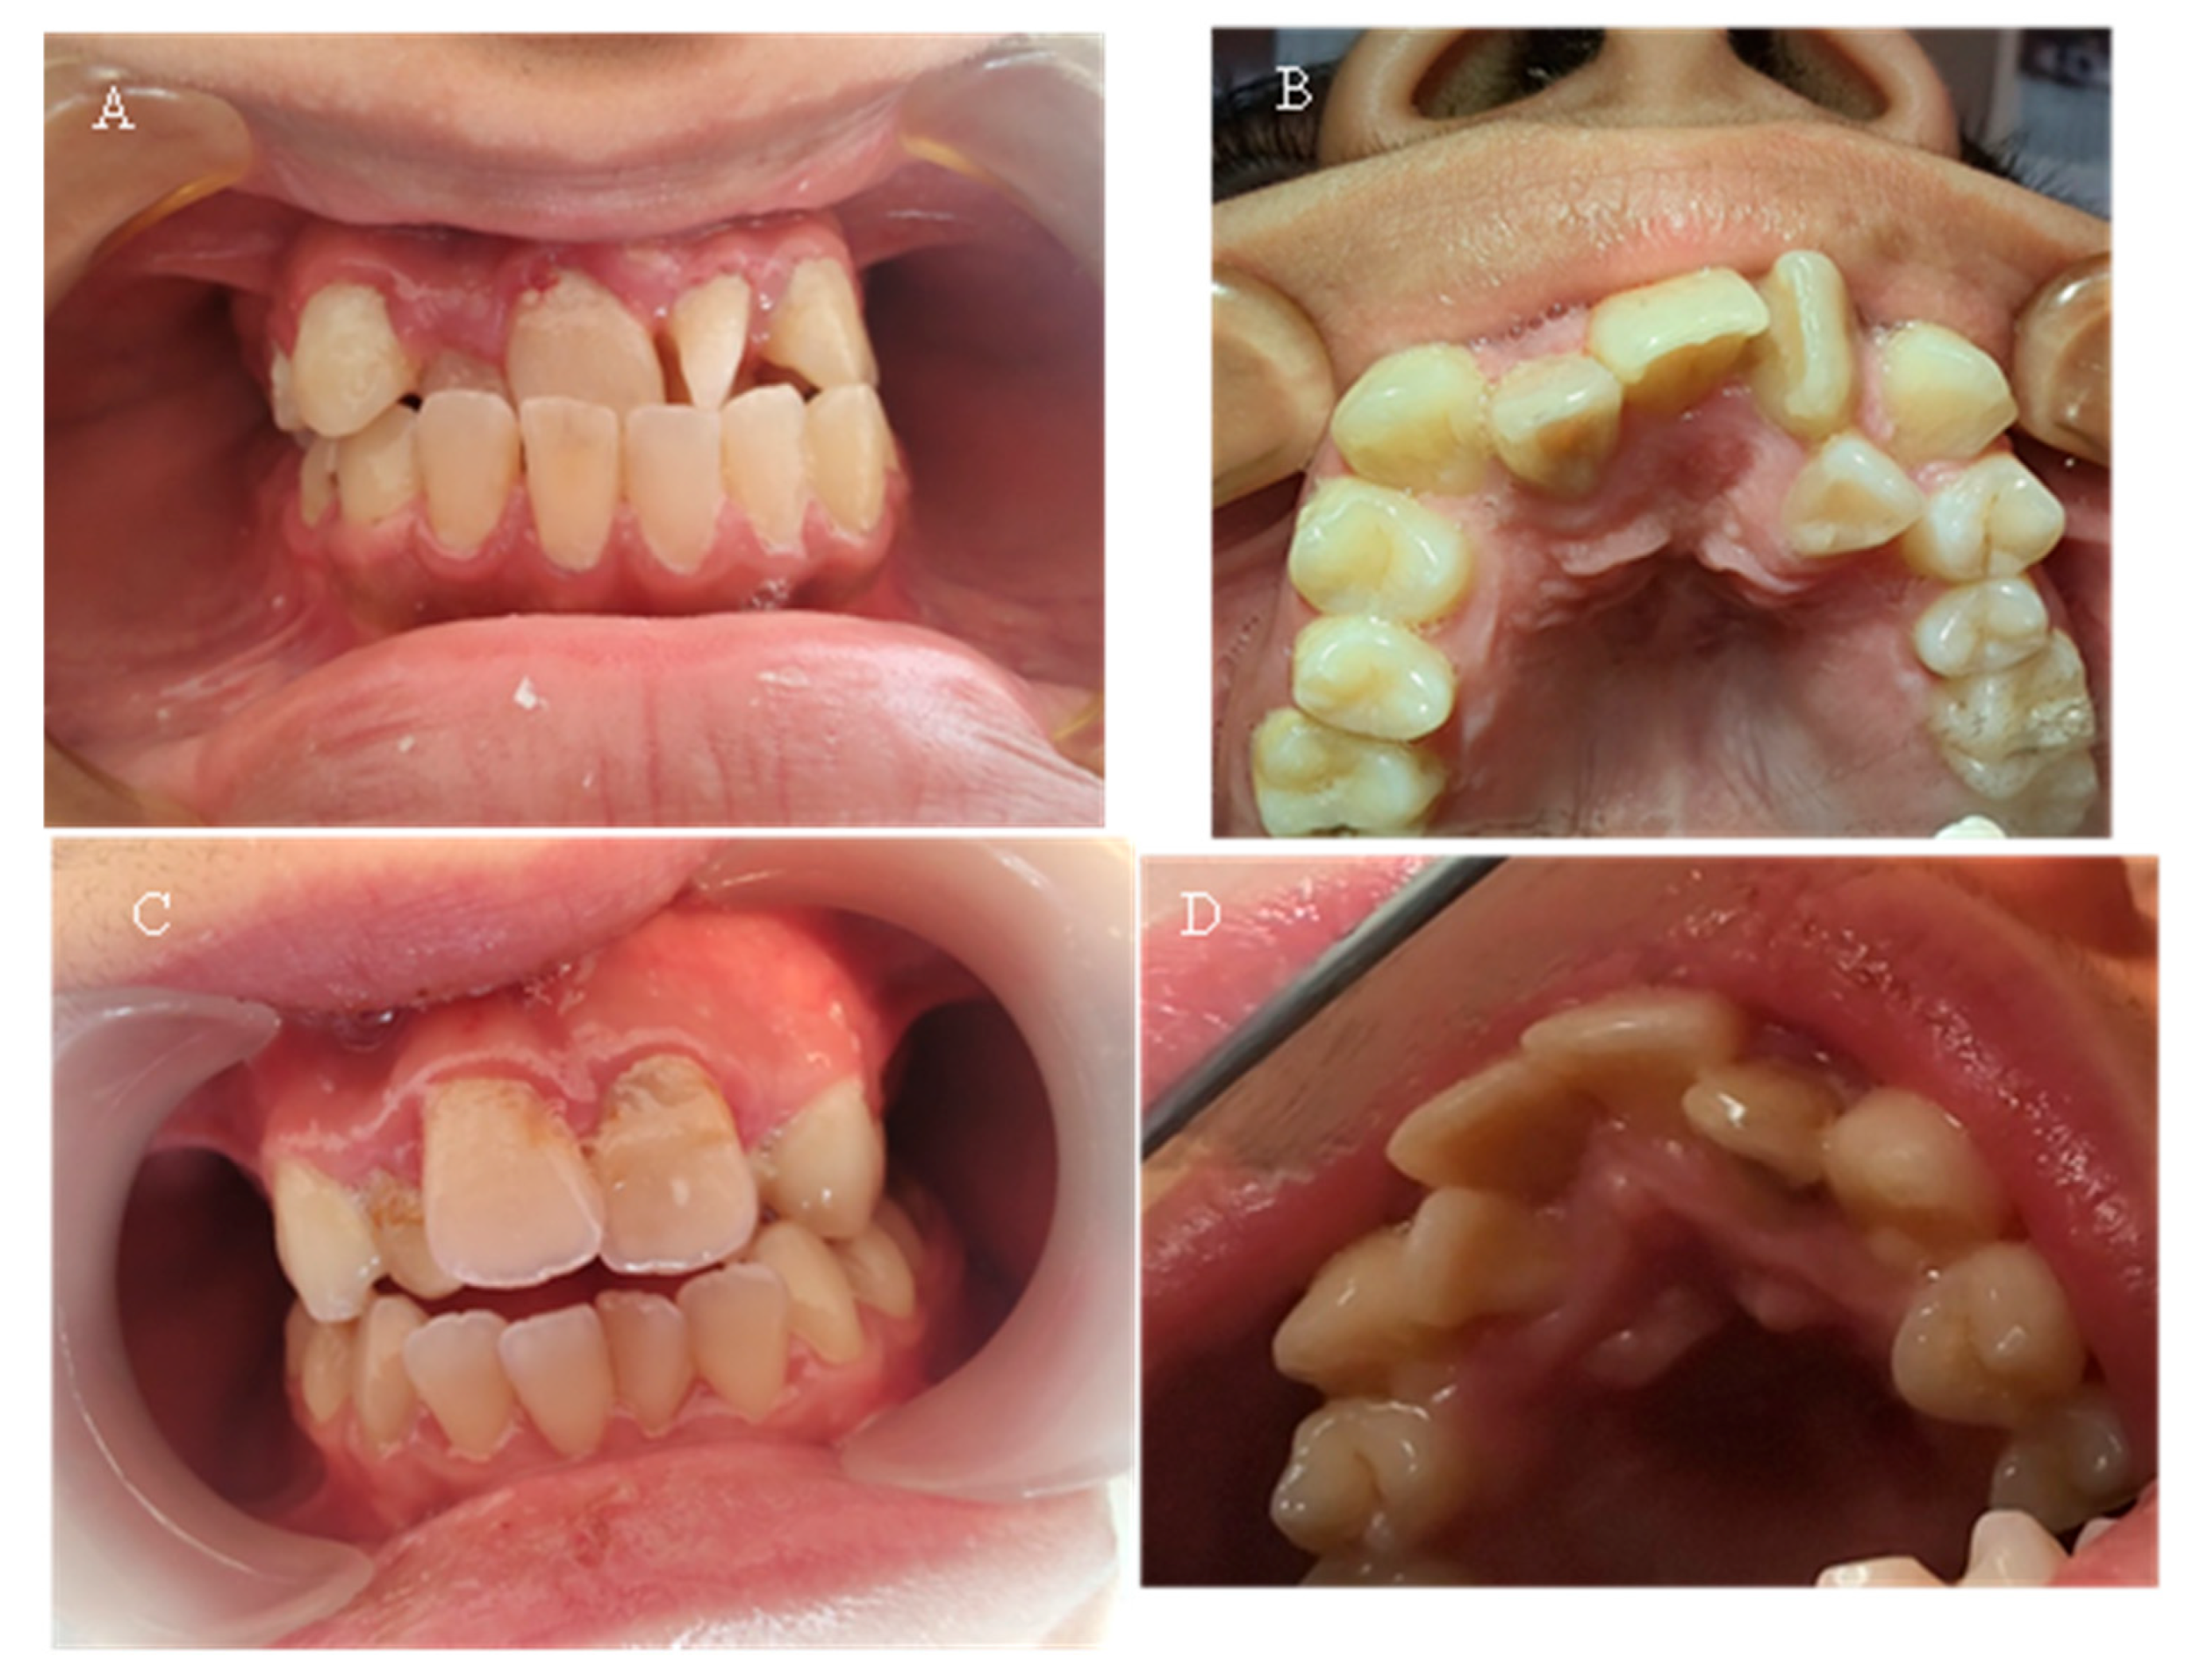

Seven of the eleven examined children were diagnosed with various types of orthodontic deformities: tooth rotations and crowding, open bite, deep bite, overjet, and crossbite in the lateral area (Figure 5). The malocclusions described in the literature, which have a probable relationship with hypophosphatemia—maxillary retrognathia and crowding in the front—were found in only two of the examined children (18.18%).

Table 5 presents the malocclusions observed in eleven children with X-linked hypophosphatemic rickets. The table details the specific types of malocclusions for each case, including overjet, open bite, maxillary retrognathia, retrusion in the front, deep bite, crossbite, crowding, and tooth rotations and crowding. Seven of the eleven children (63.64%) exhibited malocclusions, with maxillary retrognathia and retrusion in the front observed in two children (18.18%).

Figure 5. (A) Case 7—15-year-old—picture of anterior teeth in occlusion; (B) same patient—upper dental arch, occlusal picture; (C) Case 8—15-year-old—anterior teeth in occlusion; (D) same patient—upper dental arch, occlusal picture.